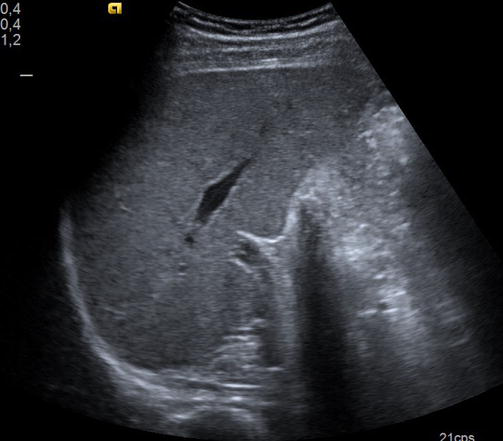

Ecografia abdominal

Estudio no invasivo que permite observar los órganos del abdomen, como el hígado, riñones, intestinos, vejiga, etc. Es útil para detectar infecciones, malformaciones o dolores sin usar radiación ni dolor.